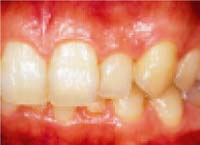

■ホームブリーチング■

施術前

施術後

「ホームブリーチング」とは歯の色を明るく・白くする治療方法です。

診療室で治療をする「オフィスブリーチング」と自宅で行う「ホームブリーチング」があります。

当院 では「ホームブリーチング」をお勧めしています。

具体的には、ご自分専用の薄型のトレーにブリーチング・ジェルを塗布し寝ている間にはめて歯を白くする方法です。

早い人で2週間目から白さを実感できます。

ゆっくりジェルを浸透させることで「自然な白さ」を手に入れられることができます。